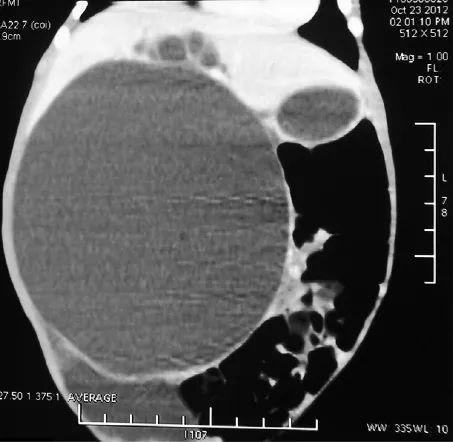

李龙-刁美团队为生后3天直径10cm巨大胆总管囊肿患儿成功进行经脐单切口腹腔镜1期根治手术,远期疗效良好,是目前世界上最小年龄、囊肿体积最大的胆总管囊肿根治手术。

生后3天直径10cm巨大胆总管囊肿,术前CT